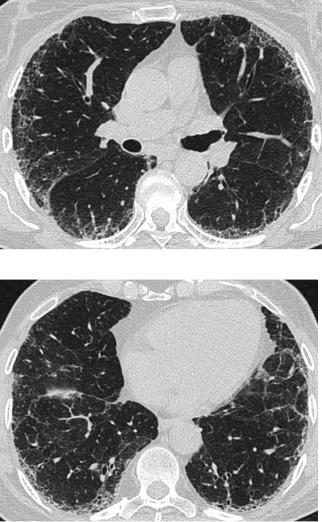

Вероятный КТ-паттерн ОИП

Распределение

Базальное и субплевральное предоминирование

Распределение часто гетерогенное

КТ-признаки

Ретикулярные изменения

Периферические тракционные бронхоэктазы/бронхиолоэктазы

Отсутствие сотового легкого

Отсутствие признаков другого ИЗЛ (неИЛФ)

Lynch D et al. Lancet Respir Med 2017; http://dx.doi.org/10.1016/S2213-2600(17)30433-2